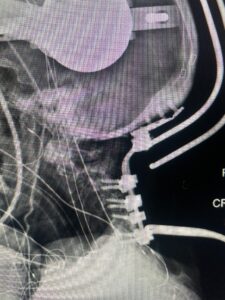

Fig 8: Intraoperative photograph demonstrating occipital-cervical construct and C1 laminectomy (blue dot). Note the 3 screws in the midline keel (blue arrow)

Cervical x-rays revealed a significantly increased atlanto-axial interval (Fig. 5) On review of her imaging studies it was noted that the right C2 isthmus was very thinned by the vertebral foramen (Figs 6a, b, and c) which would make an attempt at placing a C2 pars screw dangerous. A decision was made to perform an occipital-cervical fusion because only possible unilateral fixation and an extensive C1 laminectomy to be performed eliminating a fixation point if a more traditional C1-C2 was performed. Even if C1 lateral mass screws were able to be placed one could only perform a unilateral screw construct fixation to C2. We performed an occipital cervical fusion down to C4 to get enough inferior fixation and C1 laminectomy. The decompression went well. We placed a left unilateral pars screw and bilateral C3 and C4 lateral mass screws. We placed three 12 mm screws in the midline keel (Fig. 7). Postoperatively the patient had all around improvement in her symptoms and did not qualify for rehab. Her post op films at 6 weeks (Fig. 8)

Fig. 7: Intraoperative photograph demonstrating occipital-cervical construct and C1 laminectomy (blue dot). Note the 3 screws in the midline keel (blue arrow)

Fig. 8: Intraoperative photograph demonstrating occipital-cervical construct and C1 laminectomy (blue dot). Note the 3 screws in the midline keel (blue arrow)